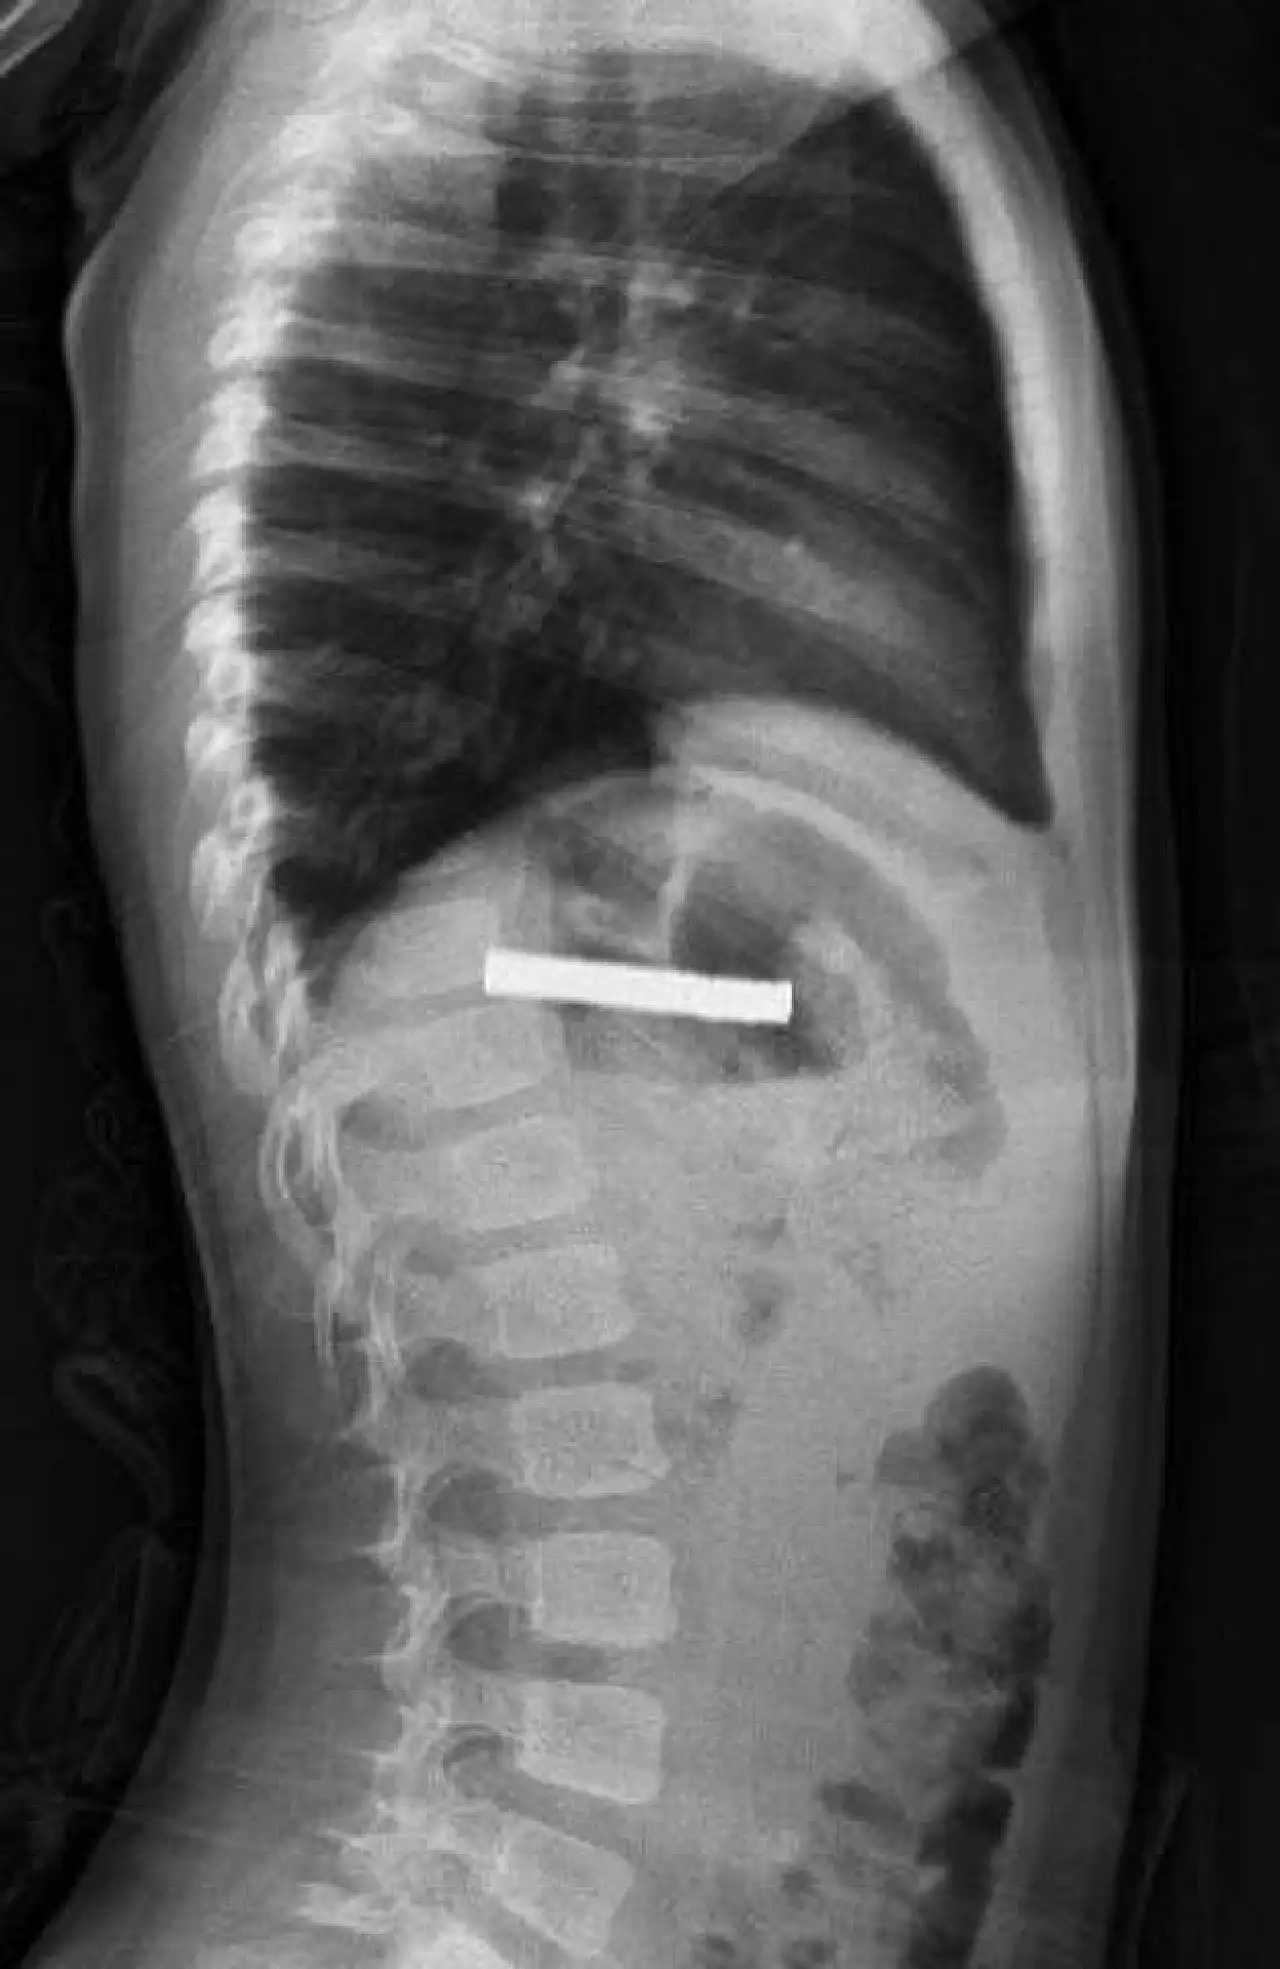

Erzurum'da evde oynarken 19 mıknatısı yutan küçük çocuk, acil müdahale sayesinde sağlığına kavuştu. Yemek borusuna yapışan mıknatıslar endoskopik yöntemle başarılı şekilde çıkarıldı.

Erzurum’da küçük bir çocuk, evde bulduğu 19 mıknatısı yuttu. Çocuğun rahatsızlanması üzerine ailesi durumu fark ederek hemen hastaneye başvurdu. Yapılan ilk müdahalenin ardından çocuk, ileri tedavi için Elazığ’daki sağlık kuruluşuna sevk edildi.Gittikleri hastanede şoku yaşadılar: Çocuğun boğazından 19 mıknatıs çıktı!

Fırat Üniversitesi Çocuk Gastroenteroloji, Hepatoloji ve Beslenme Bilim Dalı Başkanı Prof. Dr. Yaşar Doğan, yapılan endoskopik operasyonla yemek borusuna yapışmış olan 19 mıknatısı başarıyla çıkardı.Gittikleri hastanede şoku yaşadılar: Çocuğun boğazından 19 mıknatıs çıktı!

Uzun süre yemek borusunda kalan mıknatısların yol açtığı zedelenmelerin yanı sıra çocuğun genel sağlık durumunun iyi olduğu ve tedavisinin tamamlanmasının ardından taburcu edildiği bildirildi.